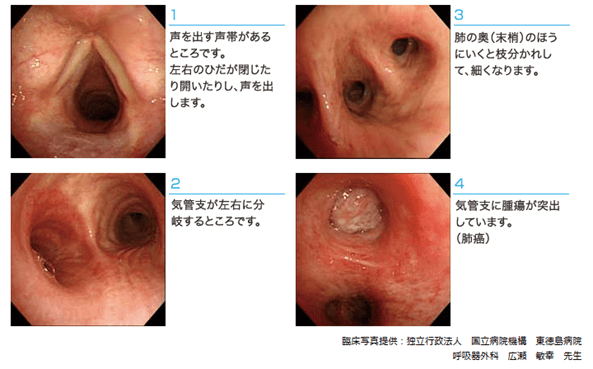

気管支鏡の観察写真